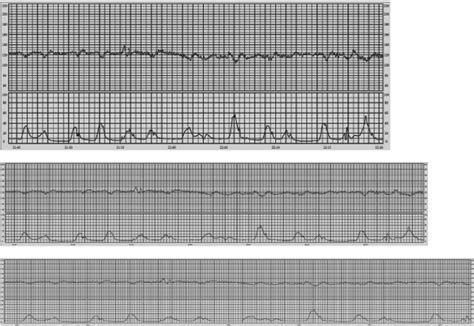

Fetal heart rate tracing recorded within 1 h prior to delivery at term